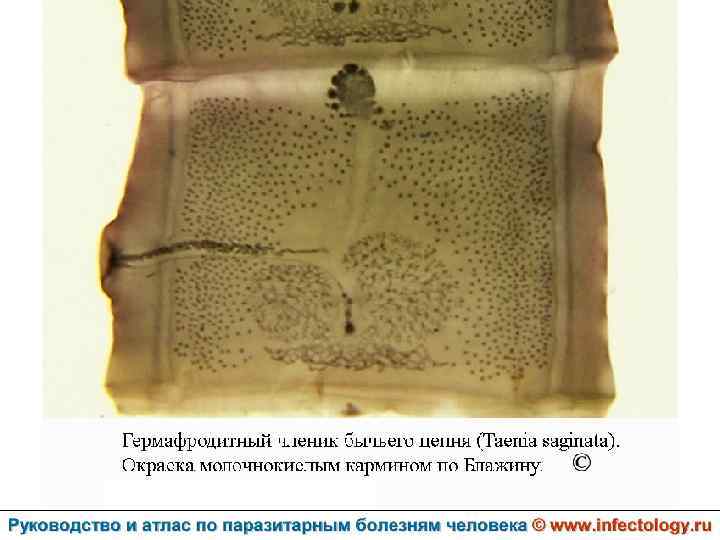

Тениаринхоз (шифр по МКБ 10 - B 68. 1) – антропонозный биогельминтоз с хроническим течением, характеризующийся преимущественно желудочно– кишечными расстройствами.